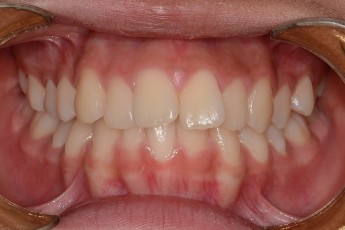

BEFORE & AFTER